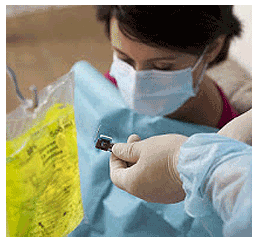

A BRIEF INTRODUCTION TO INSULIN POTENTIATION THERAPY (IPT)

A BRIEF INTRODUCTION TO INSULIN POTENTIATION THERAPY (IPT)Insulin Potentiation Therapy (IPT) is an alternative method for cancer treatment that uses insulin as a supplement with traditional chemotherapy. The advocates of this therapy claim that insulin potentiates the effectiveness of chemotherapy by lowering the dosage of chemotherapy drugs to minimize their adverse side effects. In other words, you can get the best out of your chemotherapy treatments without fearing the vicious side effects that come with it. Even though IPT has been here for more than 7 decades, the mechanism and pathway through which insulin potentiates the effects of chemotherapy is still unclear. (Read complete article)